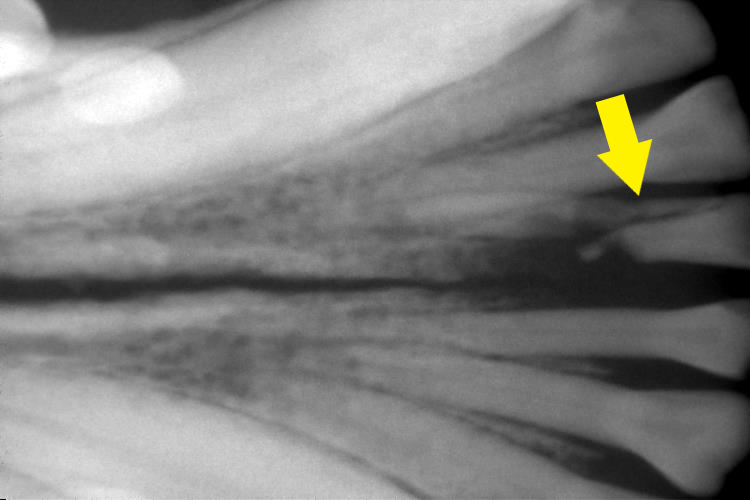

レントゲン検査

右側上顎第4前臼歯の歯根部の明らかな異常はありませんでした。

下顎切歯のぐらついていた1本は歯根破折をしていることが分かりました。